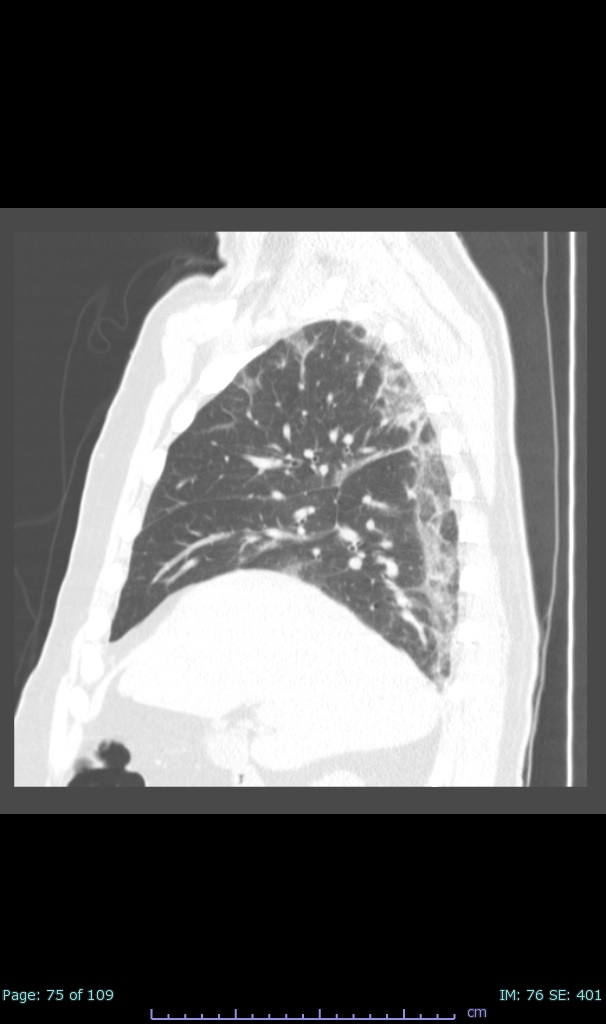

- 100% subpleural involvement, 33% + centrolobular involvement

- 40% even apical/basilar, 27% basilar dom, 5% mid dom. 1/17